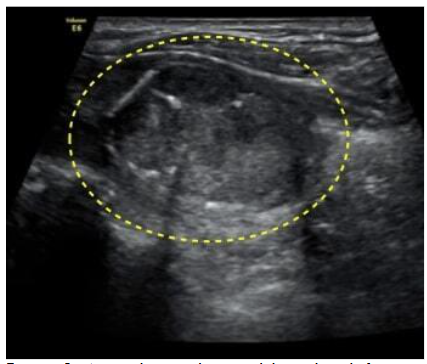

Ultrasound of the neck showed features suggestive of thyroid abscess.

A large heterogenous hypoechoic complex avascular cystic lesion(2.0x1.5x1.3cm) with thick septations and multiple air pockets with no internal vascularity in the left lobe of the thyroid.

A large heterogenous hypoechoic complex avascular cystic lesion(2.0×1.5×1.3cm) with thick septations and multiple air pockets with no internal vascularity in the left lobe of the thyroid.

Ultrasound of the neck region adequately demonstrates intra or extra-thyroid abscesses and solid or mixed thyroid gland lesions and adjacent inflammatory nodes. Thyroid abscess is rare and has unusual clinical features, so its diagnosis is often delayed. This results in complications and deadly outcomes if not diagnosed early and treated adequately. The USG neck showed a large heterogenous hypoechoic complex avascular cystic lesion with thick septations and multiple air pockets in our patient. Most often FNA could give us a clue to the diagnosis and is also a good means for identifying the bacteriologic source and for precise antibiotic selection. In our case, initial FNA could only demonstrate inflammatory cells, and no malignant cells were reported which made the differentiation of AST from Medullary thyroid carcinoma difficult in the early phases.